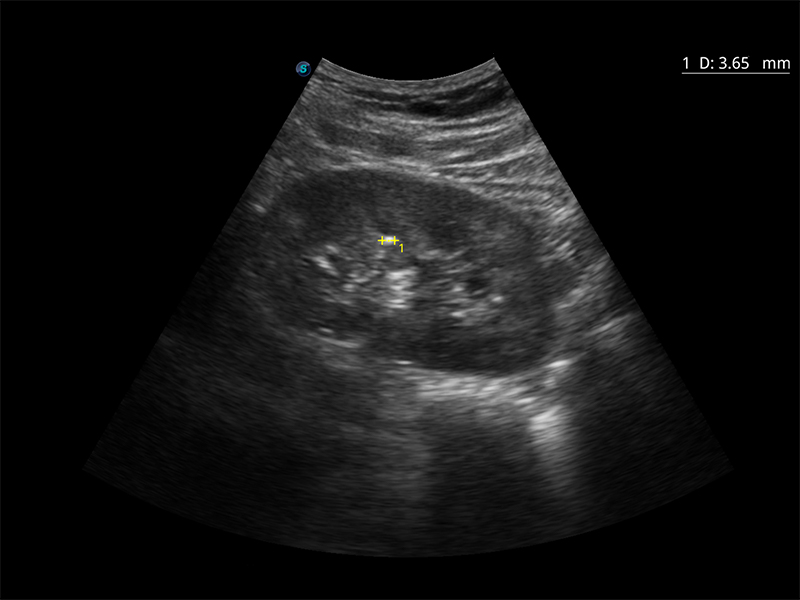

- Wide Scan per un’area dell’immagine ingrandita, utile in esami come l’ecografia ostetrica e ginecologica.